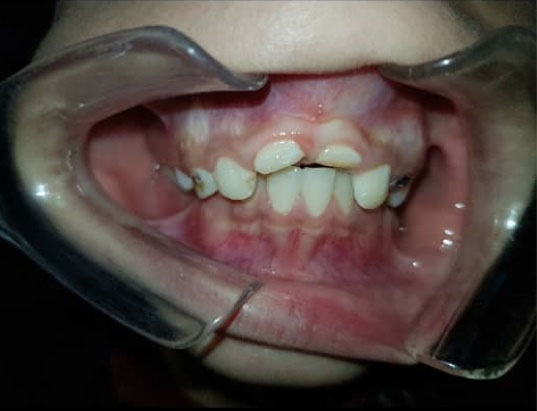

A 10-year-old boy referred to the Department of Pediatric Dentistry of Hamadan University of Medical Sciences. The chief complaints of the patient were pain and fractures of anterior teeth (Figure 1). According to his parent’s report, he had a motorcycle accident two month ago. Medical history and extraoral examination were normal. A form of informed consent was signed by parents for performing treatment procedure and presenting case report in the future. In clinical and radiographic examinations, there were no maxillary and mandibular fractures. The patient had class II malocclusion with deep bite (Figure 2). Intraoral periapical radiography revealed partial loss of the crown and oblique crown root fracture of teeth 21 and 11. The development of root apex of teeth 21 and 11 was incomplete (Figure 3). Vitality pulp tests were performed and the teeth responded negatively to electrical and thermal tests. Due to the incomplete development of roots and the time elapsed since the injury, the prescribed treatment plan was the apexification of teeth with MTA plug (Figure 4). After pulp therapy, temporary restoration was applied to the teeth 21 and 11. After multidisciplinary consultation with Pediatric Orthodontics and Periodontology departments, it was decided that a surgical extrusion was the best way to expose the fracture line. Surgical extrusion was performed for definitive treatment and reconstruction of the coronal segment because the palatal portion of the fracture line continued down to the gingival margin and was approximately 1 mm below the alveolar crest. By a periosteal elevator and a sharp carver, the teeth were gently luxated. The teeth were extruded about 4 mm by forceps which took the mesiodistal of the tooth. Due to tooth mobility at this stage, fixation in the new position was performed by a wire-composite splint (wire diameter: 0.6 m) (Figure 5). Proper antibiotic therapy was prescribed for the patient for 10 days. The patient and his parents were informed about the importance of oral hygiene and soft diet during the healing period. After two weeks, the splint was removed and the tooth mobility significantly reduced (grade I). Then, temporary tooth restoration was removed and the fiber optic post was prepared and cemented with dual-cure resin. Finally, a composite build-up was performed for maximal aesthetic outcomes (Figure 6). During the follow-up period of 2 years, no trace of root resorption was observed (Figure 7). The patient referred to the Department of Orthodontics for orthodontic treatment.

Figure 1.

Intraoral View of Teeth 11 and 21 With Crown-Root Fractures.